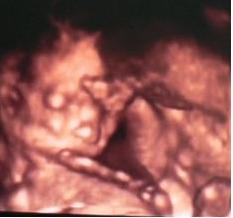

Apa csinált a 4D UH-ról képet. Persze nem a legtökéletesebb a felbontás, de megpróbálom feltenni.

Nagyon jók a képek!!! Kisfiúcskának tűnik nekem! De lehet hogy kislány! :lol: :lol: Láthatóan jól érzi magát bent. Azóta gondolom sokat nézegeted a képeket. Én napokig többször néztem mikor meg lett a fotónk, aztán lemásoltuk és kicsücsültettük a konyhaasztalra hogy sűrűn lássuk. :lol: